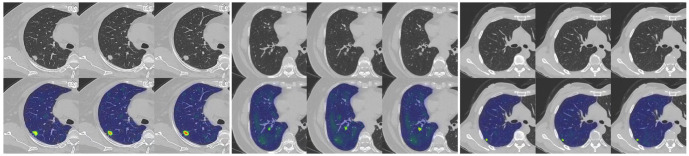

Our study has several characteristics. Technically, we mainly improved in two aspects. Firstly, we introduced an attention mechanism based on the linear BP network to fully learn the weight relationships between the four features: clinical, morphological, image, and radiomics, enabling the model to selectively focus on important features. Secondly, to address the problem of model robustness and generalization due to the small sample size, we adopted data augmentation methods from previous studies, such as sample translation and rotation, to increase the diversity of samples (38, 39). In terms of specific details, before fusing multimodal features, we utilized deep CNNs to extract deep image features of CT to capture high-dimensional representations of various features. For clinical, morphological, and radiomics features, we designed different numbers of layers of feedback neural networks to expand them into high-dimensional spaces. This approach resolved the problem of difficulty in fusing multimodal features in high-dimensional feature space. Additionally, compared to linear neural networks, the attention mechanism showed better feature fusion effects, as shown in Figure 6 , where classification accuracy increased by 3.5%, 2.7%, and 4.6% on datasets from three different hospitals. Regarding model interpretability, we utilized class activation maps to visualize the features learned by the model. Class activation map (CAM) is a technique to visualize the regions of input data that are important for predictions from CNN-based models (40). The results demonstrated that the model effectively learned local nodule features in whole-lung images and discriminated between the benign and malignant nature of GGNs through complementary information from other features. ( Figure 7 ).

Figure 7.

An example of model GRAD-CAM heat map. The top image represents the original CT image, and the bottom image represents the class activation map (CAM). In the CAM image, regions highlighted in red or yellow indicate high importance or strong activation, while regions in blue or green indicate low importance or weak activation.